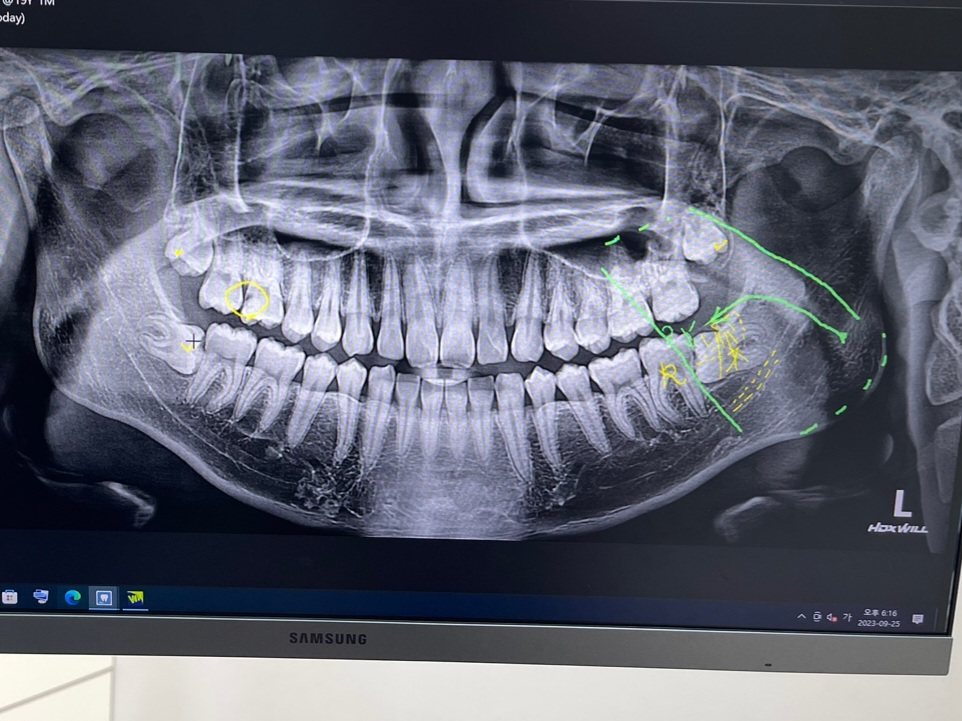

사진상에 오른쪽 위에서 2분째 치아가 신경치료를 받아야된다는 자리입니다. 다른일로 치과를 갔는데 xray를 찍고 보니까 저기에 신경치료를 해야한다네요. 진료받을때 옛날일이라 기억이 안나서 말을 못 했는데 초등학교때 저 자리에 인레이인가를 받았는데 보형물이 떨어져서 빈공간이 생긴거 같습니다. 이빨이 바뀌던 시기라 위에 부분을 안뚫고 옆에다가 바라 보형물을 고정시킨거 같고요.(당시에 신경 바로 직전이라고 했었습니다) 현재 아프지는 않은데 이런 상황을 설명해서 인레이를 하자고 하면될까요?

현재 치료가 필요하다고 보는 치아는 오른쪽 위 첫번째 큰 어금니 입니다.

과거 상황상 아직 두번째 큰 어금니가 나오지 않았을 때 첫번째 큰 어금니 옆면 충치가 있어 이를 인레이로 떼워준 것 같은데 옆면만 그렇게 인레이로 하는 게 일반적으로 흔히 하는 치료는 아닙니다. 인레이가 아니고 레진 등의 재료로 떼워준 것이 아닌가 싶습니다. 그렇다 하더라도 옆면만 덩그러니 하면 재료의 유지력이 떨어지기 때문에 실제로 탈락하기 쉽습니다. 그 상태로 이제 두번째 큰 어금니가 자라난 상황이라면 지금까지 해당 부위 위생관리가 매우 불량했을 확률이 높습니다. 음식물이 잘 꼈을텐데 이걸 제때 빼주지 않았다면 충치가 더 커졌을 확률이 높습니다.

현재 별 증상이 없다 하더라도 방사선 사진은 한번 찍어볼 필요성이 있습니다. 레진이든 인레이든 재료가 떨어진 범위가 얼마나 큰지, 신경에는 영향을 주었는지 확인해봐야 하고요

증상이 없기 때문에 신경에 영향을 줄 정도는 아니라던지 혹은 치수강(신경이 위치한 공간)이 위축되어 아직 신경까지 도달하지 않은걸 수도 있고요.

어쨌든 빈 공간에 대해서는 현재 처치가 필요할 것으로 보입니다.